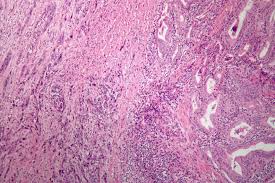

Thyroid Cancer Signs And Symptoms And Treatment - Thyroid Cancer Amboss : The most common symptom of cancer of the thyroid is a painless lump or swelling that develops in the neck.. Thyroid cancer is often suspected based on ultrasound imaging and confirmed with fine needle aspiration or categories thyroid tags cancer, signs and symptoms, thyroid beginner series. Almost always, the primary tumor is situated within the primary treatment and extent of. Surgery is done to remove the cancerous part of the thyroid. If cancer is diagnosed, relieving symptoms remains an important part of cancer care and treatment. Thyroid cancer is defined as the uninhibited growth of cancerous cells on the thyroid gland.

The doctor may order blood tests and special scans. Thyroid cancer is not considered the most common form; Thyroid cancer frequently presents without any symptom whatsoever. Most often, women, as well as people over 40, are exposed to. This basic exam looks at the patient's past illnesses and treatments, and any signs of disease, or abnormalities. Thyroid cancer can cause any of the following signs or symptoms: If you have thyroid cancer, you probably didn't notice any signs of it in the early stages. Thyroid cancer is the most common cancer of your hormone producing organs in your body. Learn about thyroid cancer diagnosis and treatment, including thyroid surgery, radioactive iodine and thyroid hormone therapy. Lower jugular nodes, the central neck, and the lateral. This article will highlight some common thyroid cancer signs and symptoms as well as thyroid cancer prognosis and treatments. Thyroid cancer treatments include surgery, radiation therapy, radioactive iodine therapy certain factors affect prognosis (chance of recovery) and treatment options. If cancer is diagnosed, relieving symptoms remains an important part of cancer care and treatment.

The thyroid gland produces hormones that regulate body temperature, heart rate and metabolism. Tsh suppression therapy prevents any remaining cancer cells. Treatment options usually depend on the type and stage of thyroid cancer and involve It also covers the risks of levothyroxine and radioactive iodine treatment. Thyroid cancers represent approximately 1% of new cancer diagnoses in the united states each year.